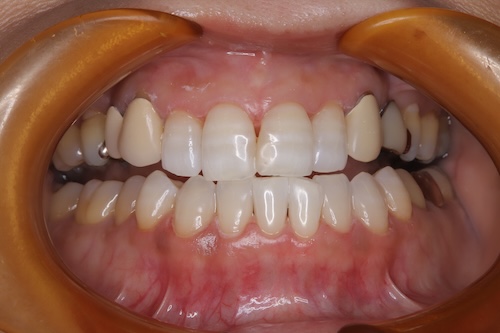

美白を目指した50代女性のホワイトニング経過と成果

50代女性 バンディング歯のお客様。 初診時シェード 右上1D3 右下3A4 目標シェードは040の歯の白さになりたいと来院された。施術内容

パーフェクト美白プラン(3ヶ月分)(税込129,800円) ・オフィスホワイトニング6回分 ・クリーニング(スタンダードケア)1回分 ・マウスピーストレー上下・付属品 ・ホームジェル5日分✕18本 ・NBベリーホワイト1本 ・NBトゥースペースト1本シェード変化

- 施術後